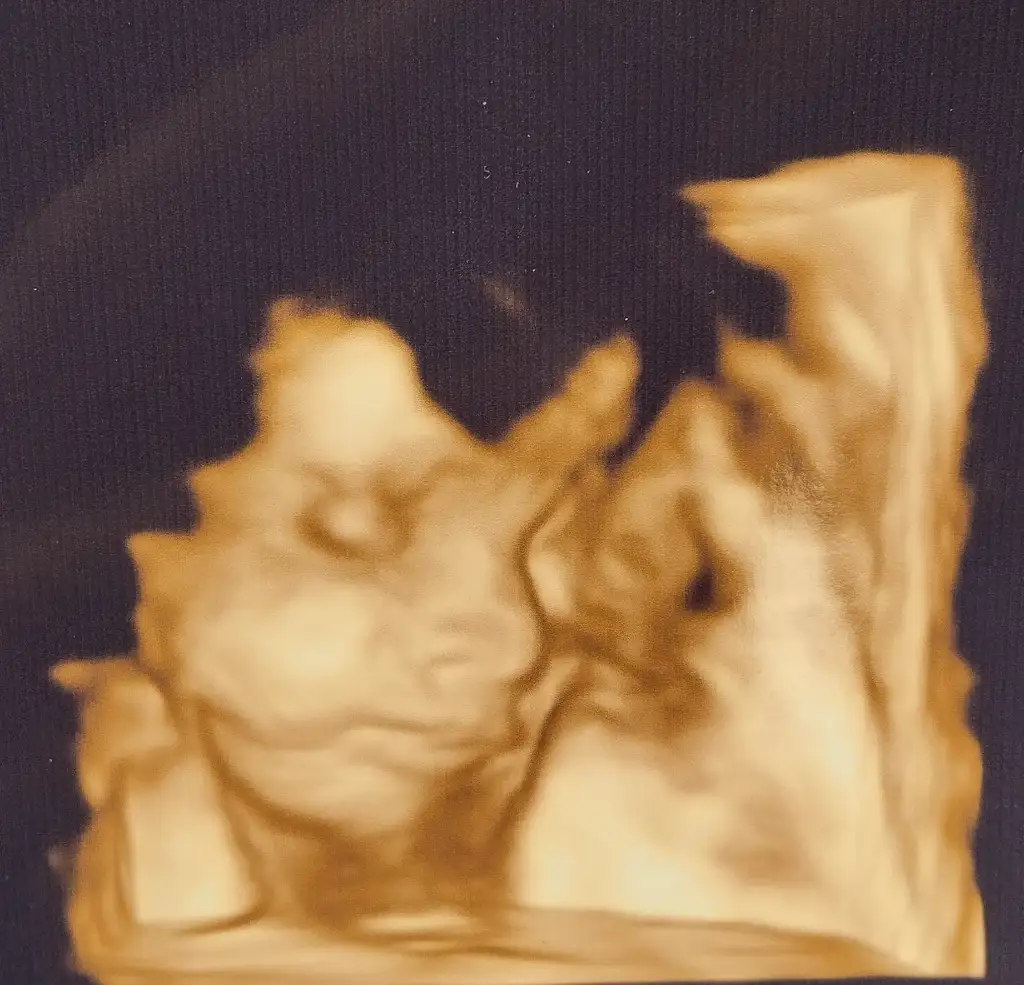

26+6dan selamlar kızlar. Bugün rutin kontrolüm vardı.

Bebik 35 cm 960 grammış. Bu da uyuklar bir hali 👯👯👯